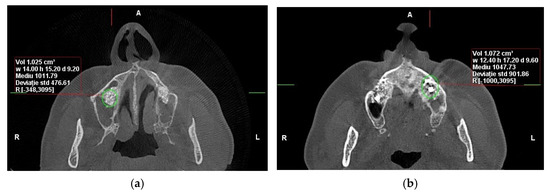

Cone-beam computed tomography (CBCT) and dual-energy X-ray absorptiometry (DEXA) scans were obtained preoperatively, immediately postoperatively, and at 6 months to assess bone volume and density. After six months of healing, bone core biopsies were collected during implant site preparation, and dental implants (Tag Medical Ltd., Kibbutz Ga’aton, Israel) were placed. A follow-up evaluation was performed 10 years after implant placement to assess long-term outcomes, including implant survival and patient-reported satisfaction. The primary analysis in this study was based on imaging and biopsy results collected within the first six months. (Figure 1). However, the 10-year follow-up data focused on long-term implant success and patient-reported outcomes rather than additional CBCT or biopsy examinations (Figure 2).

3.2. Bone Density

At six months postoperatively, CBCT analysis revealed higher mean bone density in SrR-treated sites compared with untreated controls. Over the 10-year follow-up period, SrR-treated quadrants demonstrated a mean increase of 22.94% in bone density, whereas control quadrants showed a 12.51% increase.

The Hounsfield Unit (HU) values remained consistently higher in SrR sites throughout the follow-up period, confirming a sustained enhancement in mineralization (Table 2).

At 10 years, 66.7% of SrR-treated sites demonstrated a continued increase in density compared with only 20% of controls.

These findings indicate that systemic SrR administration significantly improved bone density and mineral quality over time.

Figure 2. CBCT reconstructions in the axial plane were used to assess bone density (HU) in the area of sinus augmentation at the 10-year follow-up: (a) with RS administration, (b) without adjuvant therapy involving RS (Personal Collection).